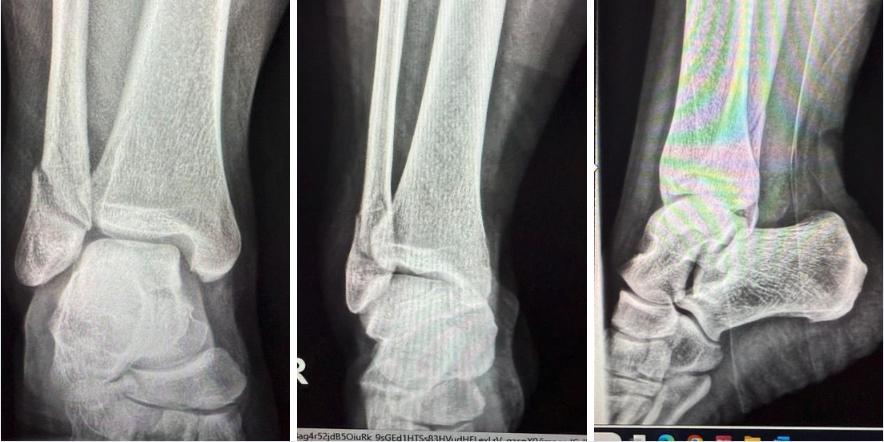

The patient was a healthy 39-year-old female who sustained a closed distal fibular fracture (Weber B type). After confirming the diagnosis radiographically and completing preoperative assessments, the team obtained informed consent. Risks reviewed included infection, bleeding, nerve injury, hardware failure, stiffness, the need for further procedures, and anesthesia-related complications, including rare, but serious, outcomes such as thromboembolism, myocardial infarction, and death. The surgeon appropriately marked the surgical site in the preoperative holding area.

Using tourniquet control and a lateral incisional approach to the fibula, careful dissection through subcutaneous tissues exposed the periosteum. A longitudinal incision of the periosteum revealed the fracture site, which the surgeon debrided and irrigated. A Weber clamp assisted with fracture reduction, confirmed intraoperatively using AP and lateral fluoroscopic views.

Fixation included a single lag screw to stabilize the long oblique fracture. A 3-hole distal anatomical fibular plate provided neutralization. Two bicortical screws inserted into the fibular shaft secured the plate proximally, and 3 locking screws affixed the distal fragment. Fluoroscopy allowed for verification of all screw positions.